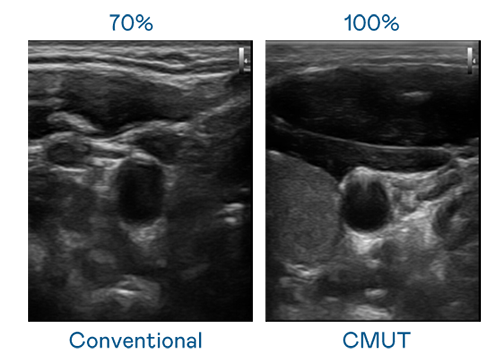

CMUT 技术是一种用电容式微机电元件来产生超音波讯号的技术。与传统 PZT 压电式技术相比,CMUT 频宽增加 30%,更宽频的超音波讯号让影像解析度大幅提升,是实现高影像品质医疗超音波扫描、促进精准医疗发展的关键技术。

超音波影像的解析度高低,首先取决于探头能发出的讯号频宽。NLC电子 CMUT 可提供高清晰的超音波讯号,提供高频宽、高灵敏度、影像纹理细节更高的超音波影像,协助医护人员缩短影像判读时间及利用精准的医疗影像进行诊断。